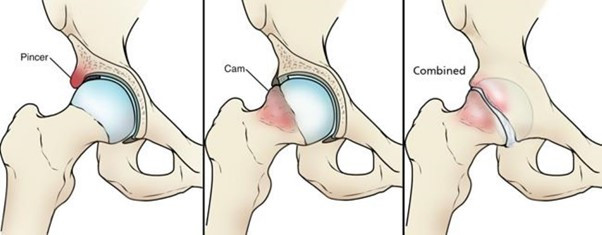

고관절충돌증후군은 말 그대로,

대퇴골 머리 부분과 비구(골반 쪽 관절) 사이에서

비정상적인 마찰이 반복되면서 생기는 질환입니다.